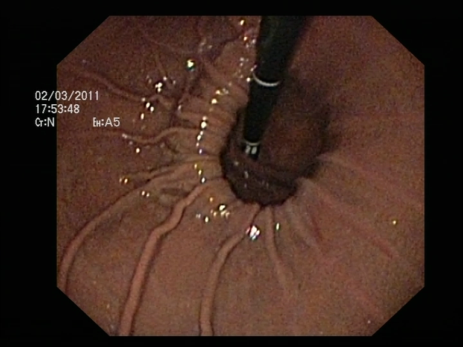

- Endoscopia digestiva alta (o esofago-gastroscopia)

: Permite confirmar la presencia de una hernia de hiato y en caso de que exista reflujo gastroesofágico evidenciar la presencia de esofagitis si la hubiera. Permite tomar biopsias para descartar lesiones premalignas en el esófago de Barret.